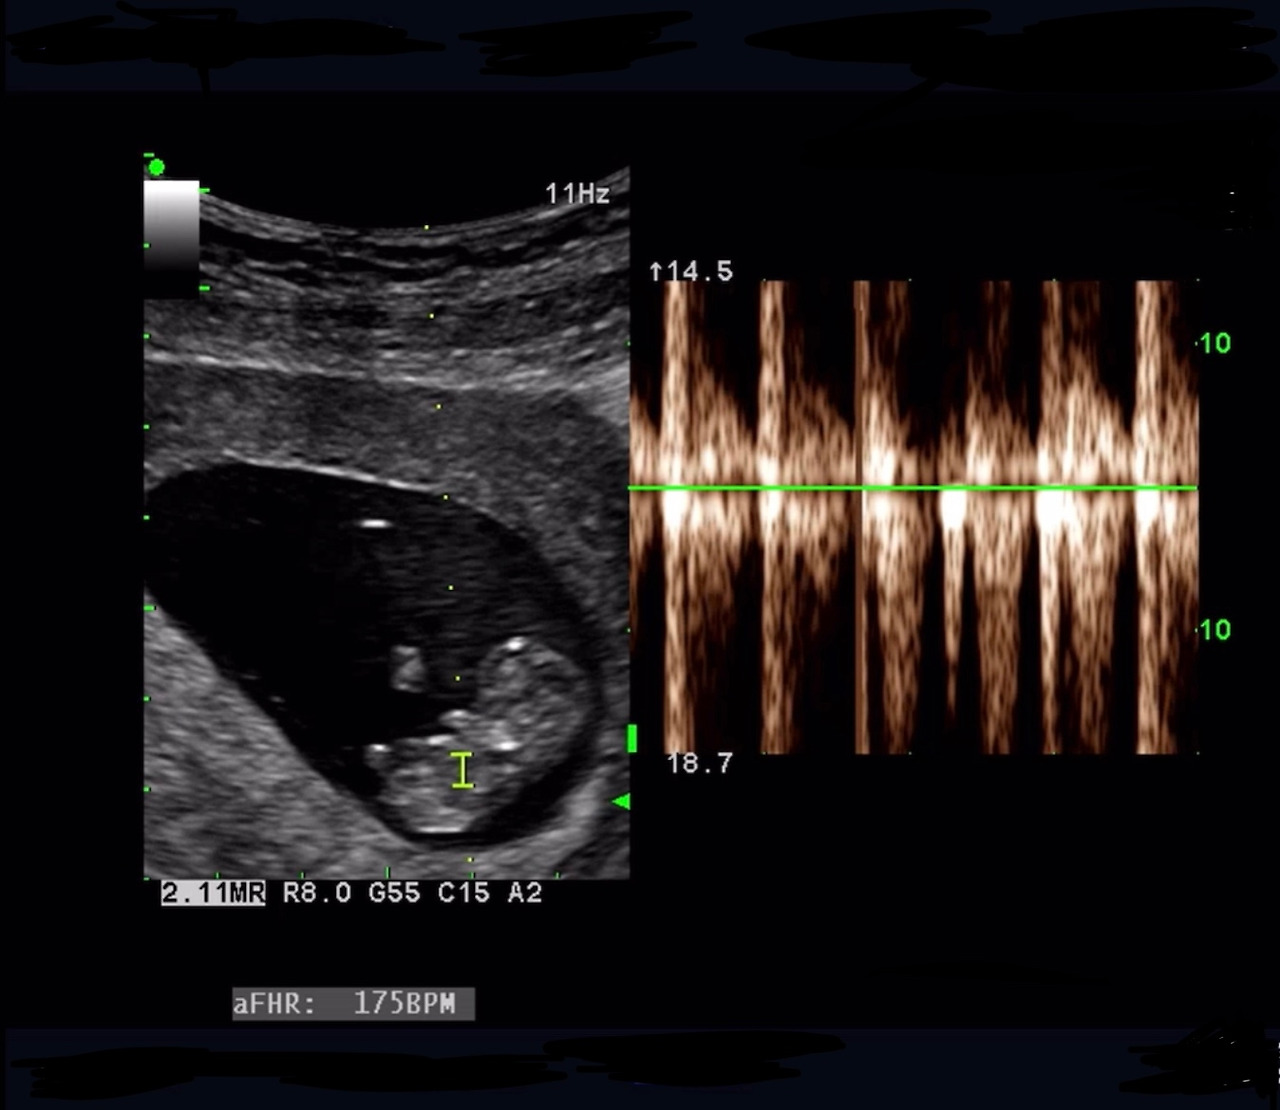

- 우리는 2년 뒤 임신을 계획했고, 결혼 4개월 만에 갑작스레 아이의 존재를 확인했다. 확인 당시 아기는 벌써 8주, 팔다리가 조금씩 나와있고 심장이 빠르게 뛰고 있었다.(남들보다 한달정도 늦게 알았달까?)

아가의 심장소리는 가슴벅찬 소리이다. 정말로 한 생명이 내안에 살아있음을 느끼게 해준다.